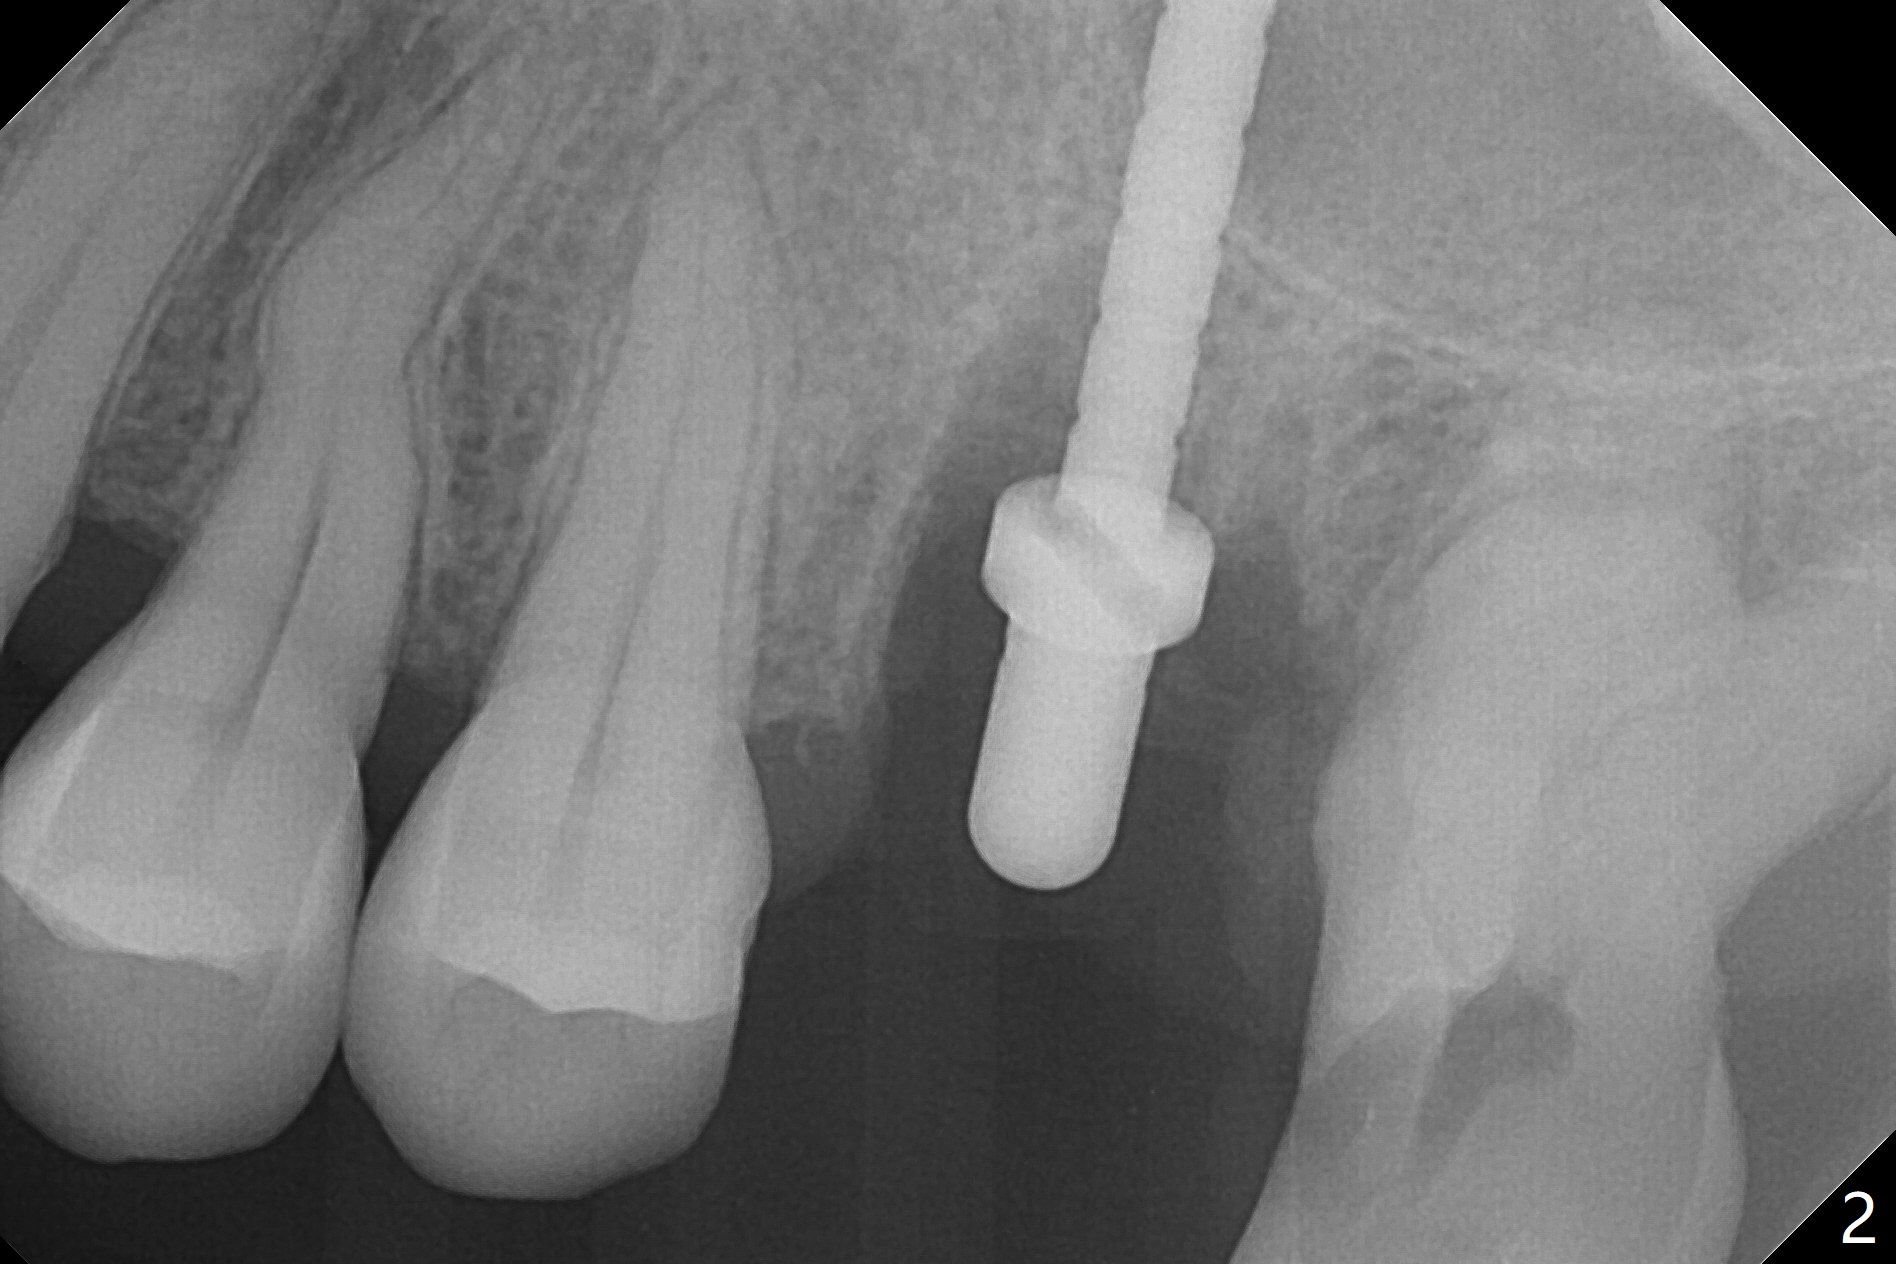

After removal of granulation tissue from the sockets associated with the fractured tooth at #14 (Fig.1 (* granulation tissue)) and initial osteotomy in the septum with a 2 mm drill for 8.5 mm, the sinus floor is penetrated by a parallel pin (Fig.2). But the sinus membrane remains intact until osteotomy finishes with a 4.8 mm drill. Following sinus lift with Vera Graft with autogenous bone (Fig.3 red *), a 5.5x10 mm implant is placed ~ 1 mm coronal to the septal crest and 1-3 mm apical to the surrounding crest (mesiodisto-buccopalatal, >55 Ncm). After further bone graft around the implant (Fig.3 white *), a 6.5x4(3) mm abutment is inserted with the 3rd round of grafting (Fig.3,4 black *). An immediate provisional is fabricated to keep the allograft in place. The implant seems to have osteointegrated 5 months postop (Fig.5).